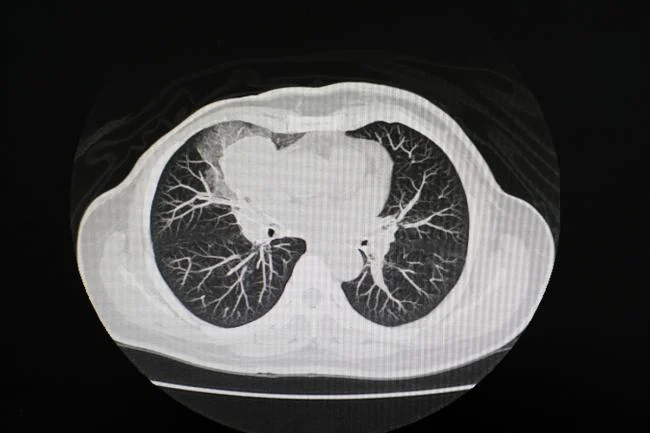

Automated CT scan analysis could fast-track clinical assessments

Adding to its impressive repertoire, the researchers further challenged Merlin to interpret CT scans of the chest—a body part entirely absent from its initial abdominal CT training material. Demonstrating remarkable cross-domain adaptability, Merlin performed as well as, or even better than, models trained exclusively on chest scans. This generalizable feature recognition capacity is a testament to Merlin’s robust architecture and training methodology, positioning it as a truly versatile diagnostic tool.